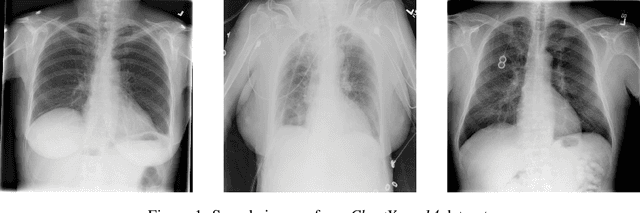

Abstract:Chest X-rays are one of the most commonly used technologies for medical diagnosis. Many deep learning models have been proposed to improve and automate the abnormality detection task on this type of data. In this paper, we propose a different approach based on image inpainting under adversarial training first introduced by Goodfellow et al. We configure the context encoder model for this task and train it over 1.1M 128x128 images from healthy X-rays. The goal of our model is to reconstruct the missing central 64x64 patch. Once the model has learned how to inpaint healthy tissue, we test its performance on images with and without abnormalities. We discuss and motivate our results considering PSNR, MSE and SSIM scores as evaluation metrics. In addition, we conduct a 2AFC observer study showing that in half of the times an expert is unable to distinguish real images from the ones reconstructed using our model. By computing and visualizing the pixel-wise difference between source and reconstructed images, we can highlight abnormalities to simplify further detection and classification tasks.

Abstract:Generative adversarial networks have been successfully applied to inpainting in natural images. However, the current state-of-the-art models have not yet been widely adopted in the medical imaging domain. In this paper, we investigate the performance of three recently published deep learning based inpainting models: context encoders, semantic image inpainting, and the contextual attention model, applied to chest x-rays, as the chest exam is the most commonly performed radiological procedure. We train these generative models on 1.2M 128 $\times$ 128 patches from 60K healthy x-rays, and learn to predict the center 64 $\times$ 64 region in each patch. We test the models on both the healthy and abnormal radiographs. We evaluate the results by visual inspection and comparing the PSNR scores. The outputs of the models are in most cases highly realistic. We show that the methods have potential to enhance and detect abnormalities. In addition, we perform a 2AFC observer study and show that an experienced human observer performs poorly in detecting inpainted regions, particularly those generated by the contextual attention model.